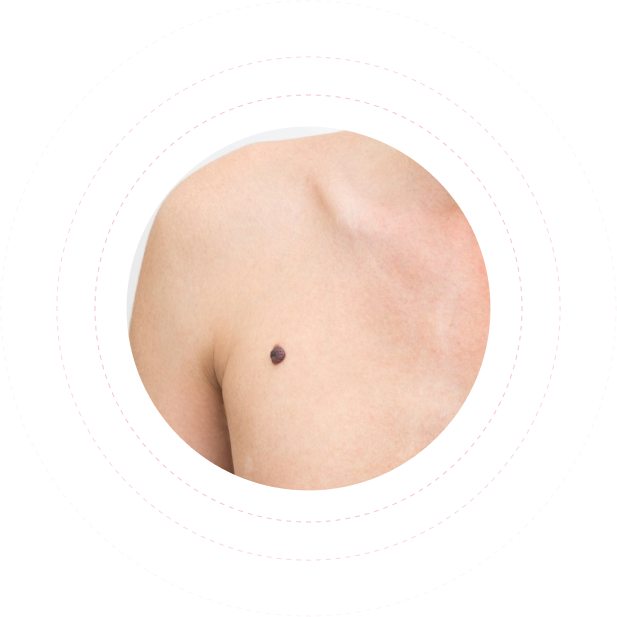

Это – интеллектуальная машина, фотографирует ваше тело и заносит в программу все родинки – невусы, пигментные пятна, уплотнения, папилломы – все, что может принести коже вред, переродившись в опасную патогенную форму.

Меланома - злокачественная опухоль, развивающаяся из меланоцитов

- пигментных клеток, продуцирующих меланины.

Наряду с плоскоклеточным и базальноклеточным

раком кожи относится к злокачественным опухолям кожи